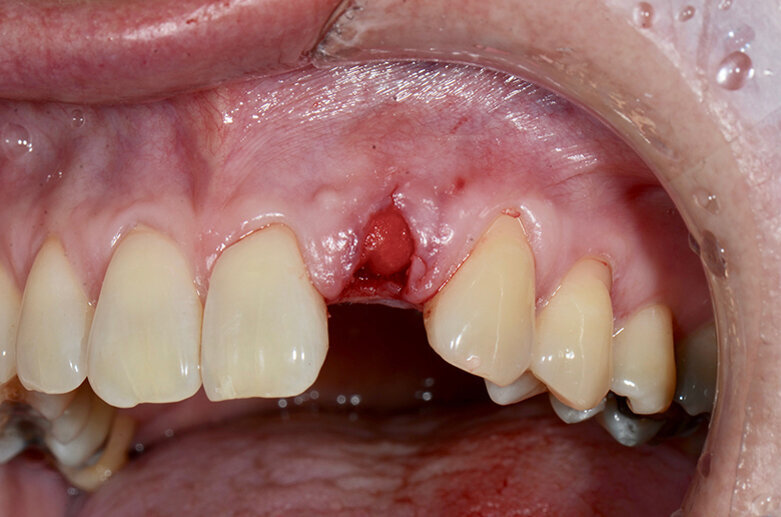

A 48-year-old male patient presented with a horizontal fracture of tooth #22 (Fig. 1). He complained of swelling of the tooth’s periapical area, and the periapical radiograph revealed a horizontal fracture with an unfavourable root–crown ratio (Fig. 2).

Fig. 3: Clinical view after extraction of fractured tooth #22.